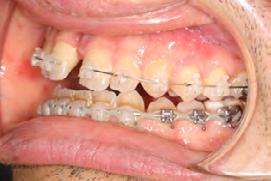

Approximately six months after insertion of the RPE, digital scans were taken for SureSmile custom wires and the patient was scheduled for the SFOT procedure with the oral surgeon. The RPE was removed, SureSmile wires inserted and segmental corticotomies performed, immediately followed by further vertical elastics on the right side (Figure

4). Archwires were upgraded incrementally into 19 x 25 SS. Once the bite was completely closed, the patient was referred to the myofunctional therapist to begin treatment. Eight sessions of myofunctional exercises were performed, focusing on muscle building, toning, synchronicity and awareness. Improvement in correct chewing, swallowing and resting postures of the lip and tongue were addressed. All appliances were removed 21 months after initial insertion (Figure 5), and the patient was referred to a re-

Figure 4. Post-corticotomy, with SureSmile custom wires.